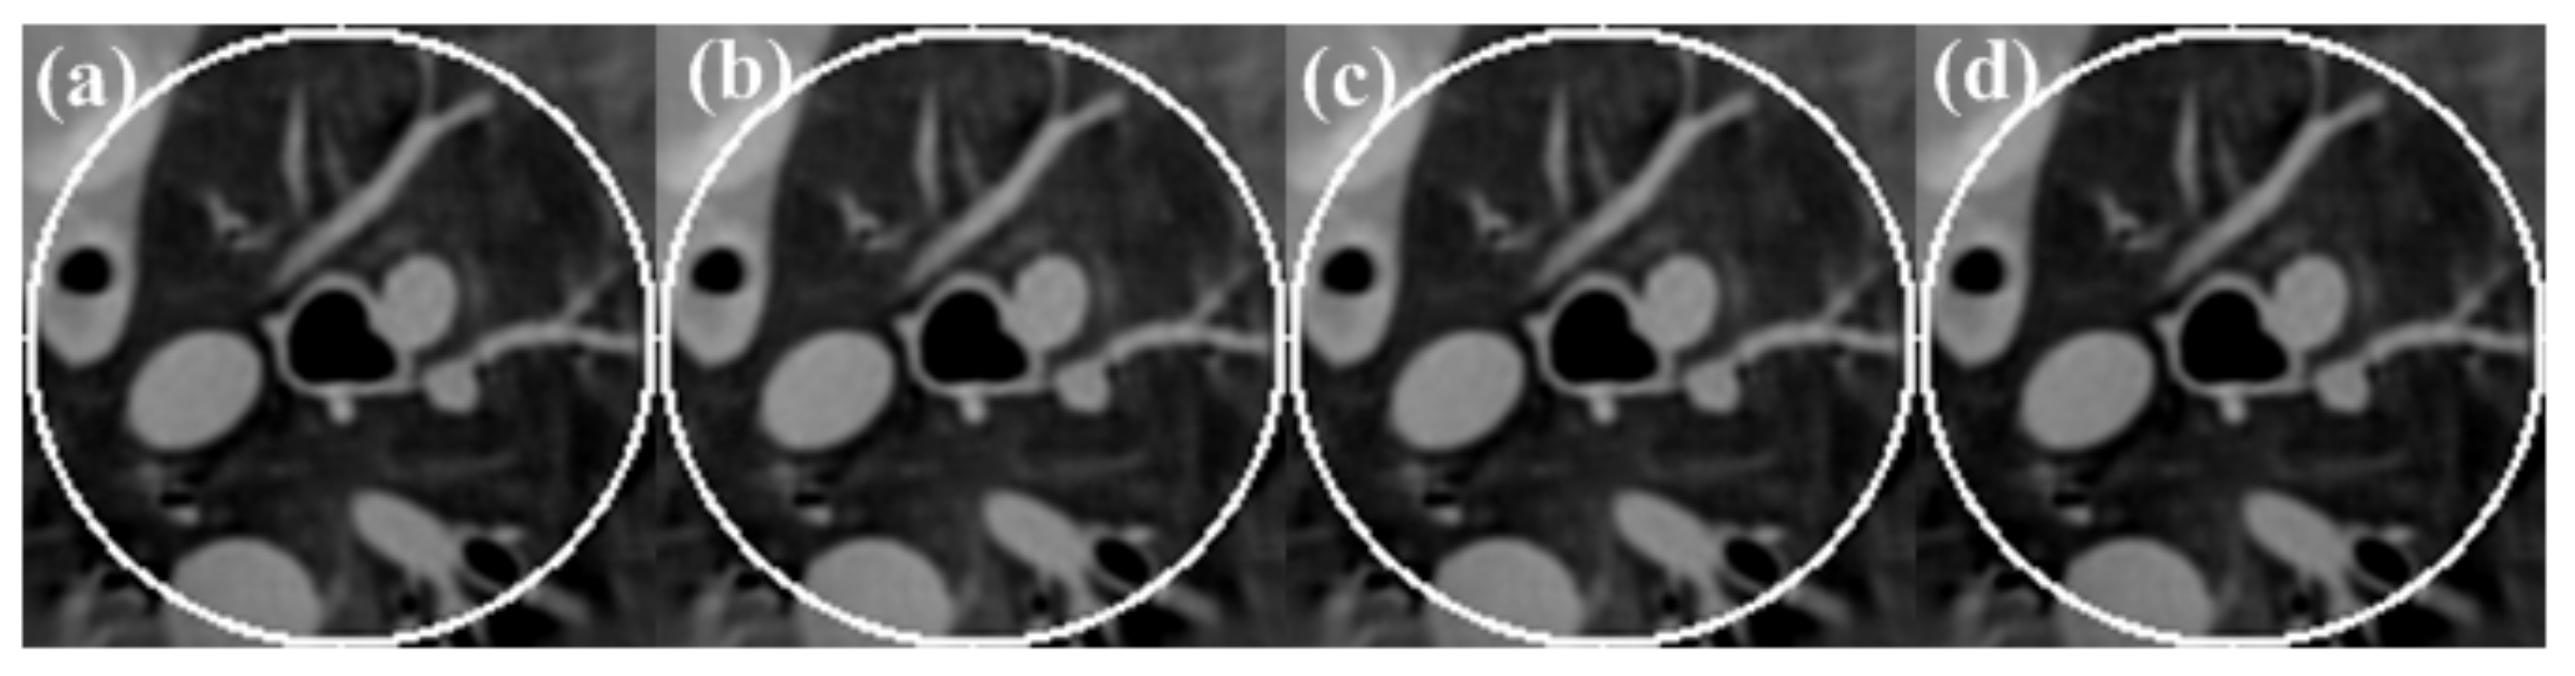

To investigate the effect on the accuracy of an estimated DC value on the recovery of an intensity drop, the reconstructed ROIs from the normal-dose sinogram with four different DC values near the true value are shown in Figure 10. The corresponding central horizontal and vertical profiles are shown in Figure 11. It can be seen that the proposed algorithm is robust with respect to the DC value.

Figure 10.

Reconstruction results with different DC: (a) DC = 2900; (b) DC = 3000; (c) DC = 3100; (d) DC = 3200. The display window is [−700 800]HU.

The DC value of the cross-section where the ROI region is located needed to be calculated. In this paper, we used the untruncated projection data to calculate the value. Figure 10 and Figure 11 illustrate that the DC value of the cross-section image has little effect on the reconstruction results. In fact, we can use the truncated data to estimate the DC value. For example, we can estimate the ratio of the area of a cross-section of the human body to the area of the organ of interest; then, we can estimate the DC value of the whole cross-section using the DC value of the projection through the ROI region and the above ratio. The next step is to use the truncated projection data to estimate the DC component of the image of the cross-section where the ROI region is located.